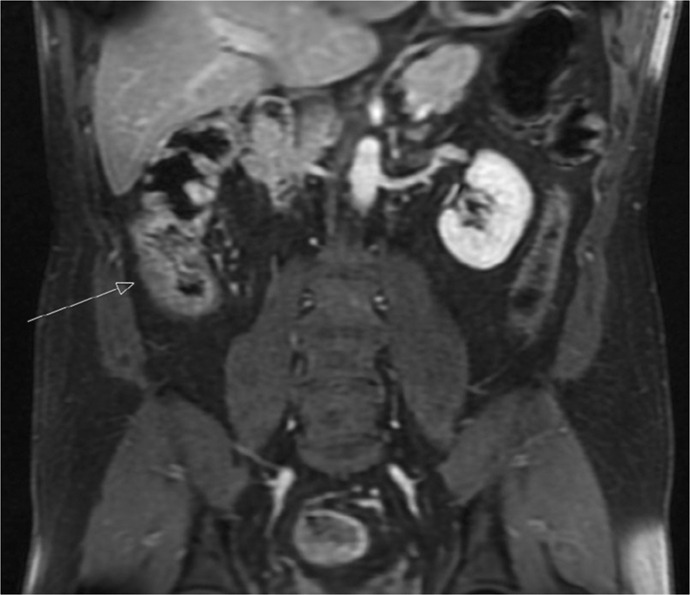

Case presentation: This case report presents a challenging case of a young man presenting with symptoms of abdominal pain, nausea, vomiting and non-specific symptoms of lethargy and fatigue. The case describes overlapping features with granulomatosis with polyangiitis (GPA) and anti-neutrophil cytoplasmic antibodies (ANCA)-positive and -negative vasculitis. The patient needed extensive workup and investigations to be eventually diagnosed with EGPA. In this case, myeloperoxidase (MPO) ANCA was negative, which is positive in the majority of EGPA cases, and this poses an additional diagnostic dilemma.